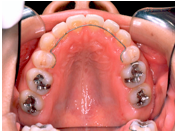

• 歯を抜くかどうかは、矯正治療をする上で非常に重要な問題です。そこで、治療方針を決める際にはまず検査をし、その検査結果を分析します。もちろん患者さんの希望も考慮にいれて、診断の際に最終的な判断をします。

• 歯を抜く場合には、どうして抜かないといけないのか、何本抜くのか、またどの歯を、いつ、どこの歯科医院で抜くのか(当クリニックでは、抜歯はゆきつけの歯科医院へお願いしています)などを分析資料を交えて説明致します。抜歯したスペースは、矯正治療によりどのように利用されますので、隙間が残ることはまずありません。抜く場合にはそれによりかみ合わせや、横顔等がどう変化するのかも、予測画像をお見せすることもできます。